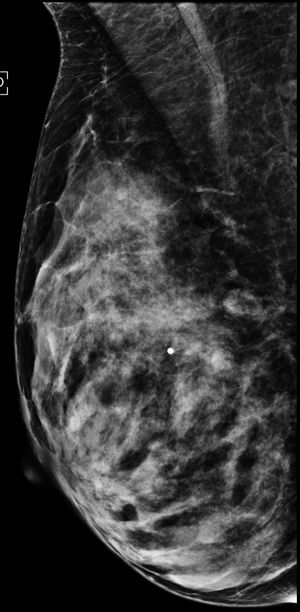

Image IQ: Screening Ultrasound for Dense BreastsByStamatia Destounis, MDNovember 4th 201647-year-old patient offered screening ultrasound due to dense breast tissue.